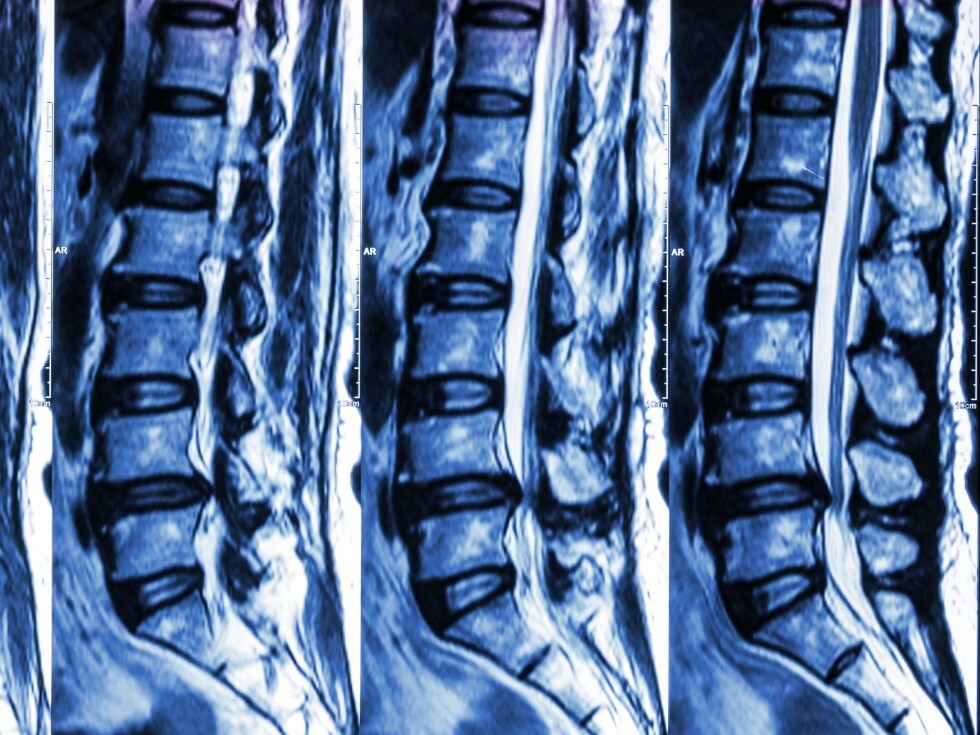

MRI - Spine

What is an MRI of the spine?

MRI of Lumbar Spine

MRI Lumbar Spine

Magnetic resonance imaging, or MRI, is a method of producing detailed pictures of organs and body tissues by exposing a patient to radio waves in a strong magnetic field. The field is measured and analyzed by a computer, which forms two- or three-dimensional images that may be viewed on a monitor. Because it uses radio waves and a magnetic field rather than x-rays, there is no exposure to radiation. An MRI of the spine is able to detect both normal and abnormal tissue and often makes it possible to determine the cause of back pain.

Why might my doctor recommend an MRI of the spine?

If you experience persistent back and leg pain, an MRI of the spine may be recommended by your doctor to detect bulging, degenerated or herniated disks. It also can be used to pinpoint compressed, or pinched, nerves. Additionally, an MRI of the spine is often used before surgeries to help in the planning process and then used again after surgery to look for changes and any scarring or infection.